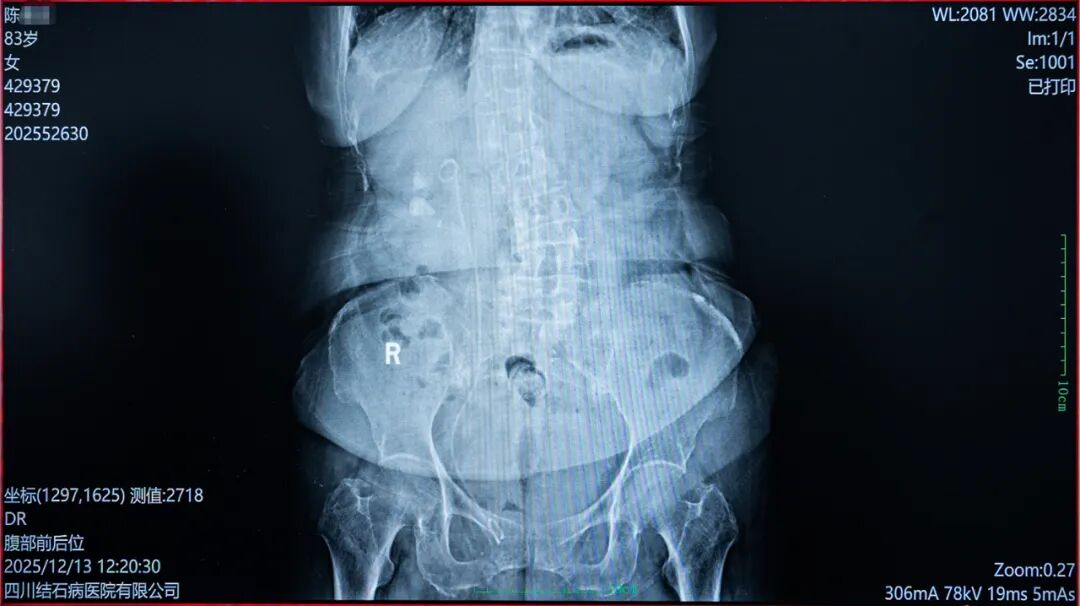

经过一个多月的休养,陈奶奶的身体情况得到了极大改善。12月上旬,她再次来到四川结石病医院。二期手术过程中,常立高教授运用高清视野与铥激光设备,将患者右肾中下盏的结石“粉末化”击碎,并配合智能负压清石系统,以“边碎边吸、同步清空”的方式,为患者成功解除结石病痛。

△第二期手术后